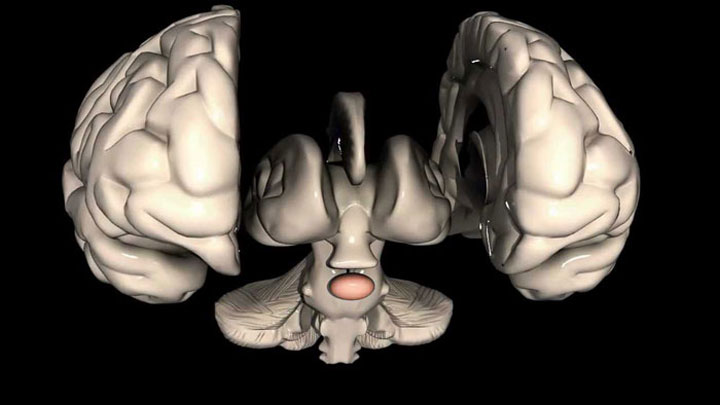

غده هیپوفیز کوچک و شبیه بیضی است و زیر دماغ در قسمت درونی مغز قرار گرفته است. غده هیپوفیز و هیپوتالاموس با ساختاری ساقهمانند به هم متصل هستند. هیپوتالاموس، بخش کوچکی از مغز است و در ایجاد تعادل میان عملکردهای مختلف بدن نقش دارد. هیپوتالاموس میزان ترشح هورمونها از هیپوفیز را هم کنترل میکند. غده هیپوفیز به ۲ بخش لوب پسین و پیشین تقسیم میشود.